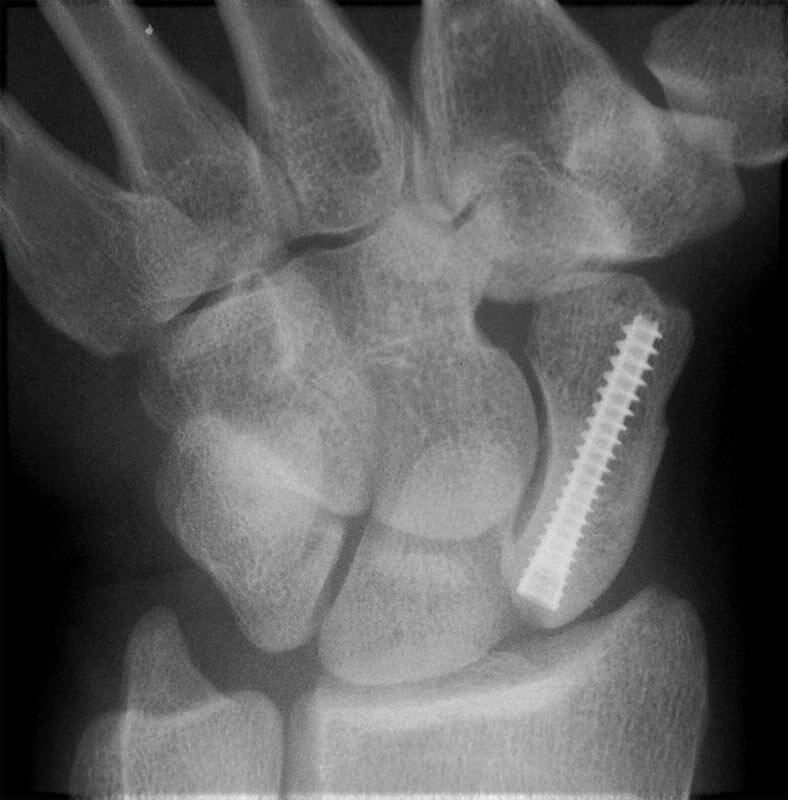

The patient must perform an X-ray to be able to quantify the degree of wear of the joint.

Arthroplasty:Replacing the joint at the base of the thumb has a long history, but the technique is still evolving. The purpose of the intervention is to maintain the mobile joint, maintaining a good mechanical function of the foot.

There are different surgical options and adapted prostheses: total arthroplasty in which both joint surfaces are replaced, replacement of a part of the joint (hemiarthroplasty), or silastic joints with hinges, where there is a flexible continuation of a spacer material in the joint space.

.jpg)

This procedure is used for advanced osteoarthritis in patients who do not want an arthrodesis. An arthroplasty has the advantage of maintaining minimal movement in the joint (although its practical effects are not so great, compared to a fusion of the thumb). The operation has a special advantage, that there is the possibility to wear heels postoperatively. The disadvantage of the procedure is that, as with all arthroplasties, the prosthesis eventually deteriorates and needs to be replaced, and the time varies depending on use, weight, and type of arthroplasty.

At 6 weeks postoperatively, an X-ray is necessary to see how the affected joint heals. Driving is allowed after 6 weeks, and hard physical work after 12 weeks.